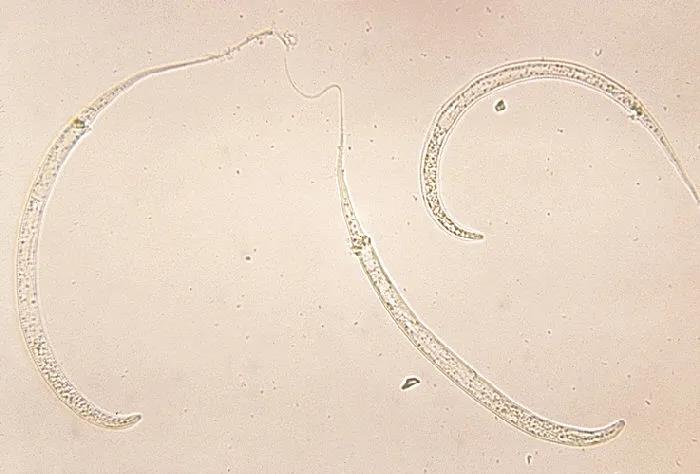

麦地那龙线虫 | CDC / Wikimedia Commons

这种生物就犹如它的名字一样让我们一头雾水,它到底是什么生物?是龙还是虫?而它的名字也困惑了我好久,到底是麦地那·龙线虫还是麦地那龙·线虫?拉丁文学名Dracunculus medinensis揭示了答案:麦地那·龙线虫才是正确的读法。

最大的线虫

龙的体型非常巨大,而继承龙之名的麦地那龙线虫,同样也是已知最大的线虫之一,体长可以超过一米。我们的祖先有一句至理名言:“不怕贼偷就怕贼惦记。”试想在不知不觉当中,你体内潜伏着一条“恶龙”,它不仅无情的吞噬着你的血肉,还会在未来的某一天释放强烈的“暗黑魔法”让你痛不欲生,想想就会让我不寒而栗......

麦地那龙线虫的幼虫生活在水中,它们会寄生在一些微小的桡足类动物(通常俗称为剑水蚤,大型种类也被作为观赏鱼的活饲料也将其称为青蹦)体内,当人喝了含有剑水蚤的水,就会被感染。剑水蚤被胃液消化掉后,龙线虫的幼虫会钻入消化道的表皮,通过循环系统进入你的体内,吸收人体组织生长发育。当然“恶龙”会分泌一些物质混过免疫系统,同时也抵消疼痛感,这样即使恶龙的体长达到1米,我们也不会察觉到它的存在......